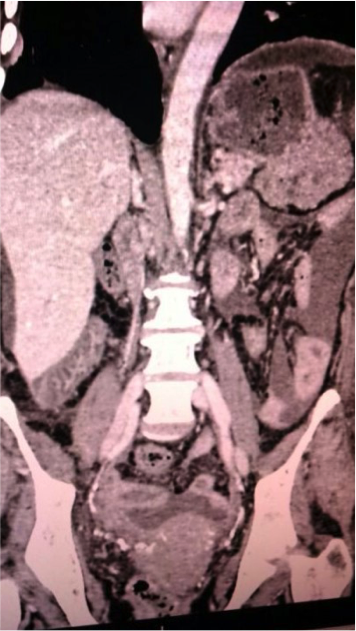

Paciente mujer de 56 años, con antecedente de Enfermedad Renal Crónica (ERC) en (DP) continua ambulatoria durante 2 años. Ingresó a emergencia por dolor abdominal, náuseas, vómitos y disminución en el drenaje de líquido peritoneal de 5 días de evolución. Se evidenció incremento del dolor abdominal al infundir líquido de DP, además de drenaje sanguinolento, sospechándose peritonitis, por lo que se procedió a la toma de muestras (Tabla 1) y se inició tratamiento con antibióticoterapia empírica, además de cambio de modalidad de terapia de reemplazo renal a hemodiálisis. (Figura 1)

Ecografía y tomografía abdominal (Figura 1)

Masa lobulada en cola de páncreas, posterior a fondo y           cuerpo gástrico sin infiltración

Figura 1. Tomografía abdominal. Se observa masa lobulada en cola de páncreas, posterior a fondo y cuerpo gástrico sin infiltración. (59x44x64 cm)